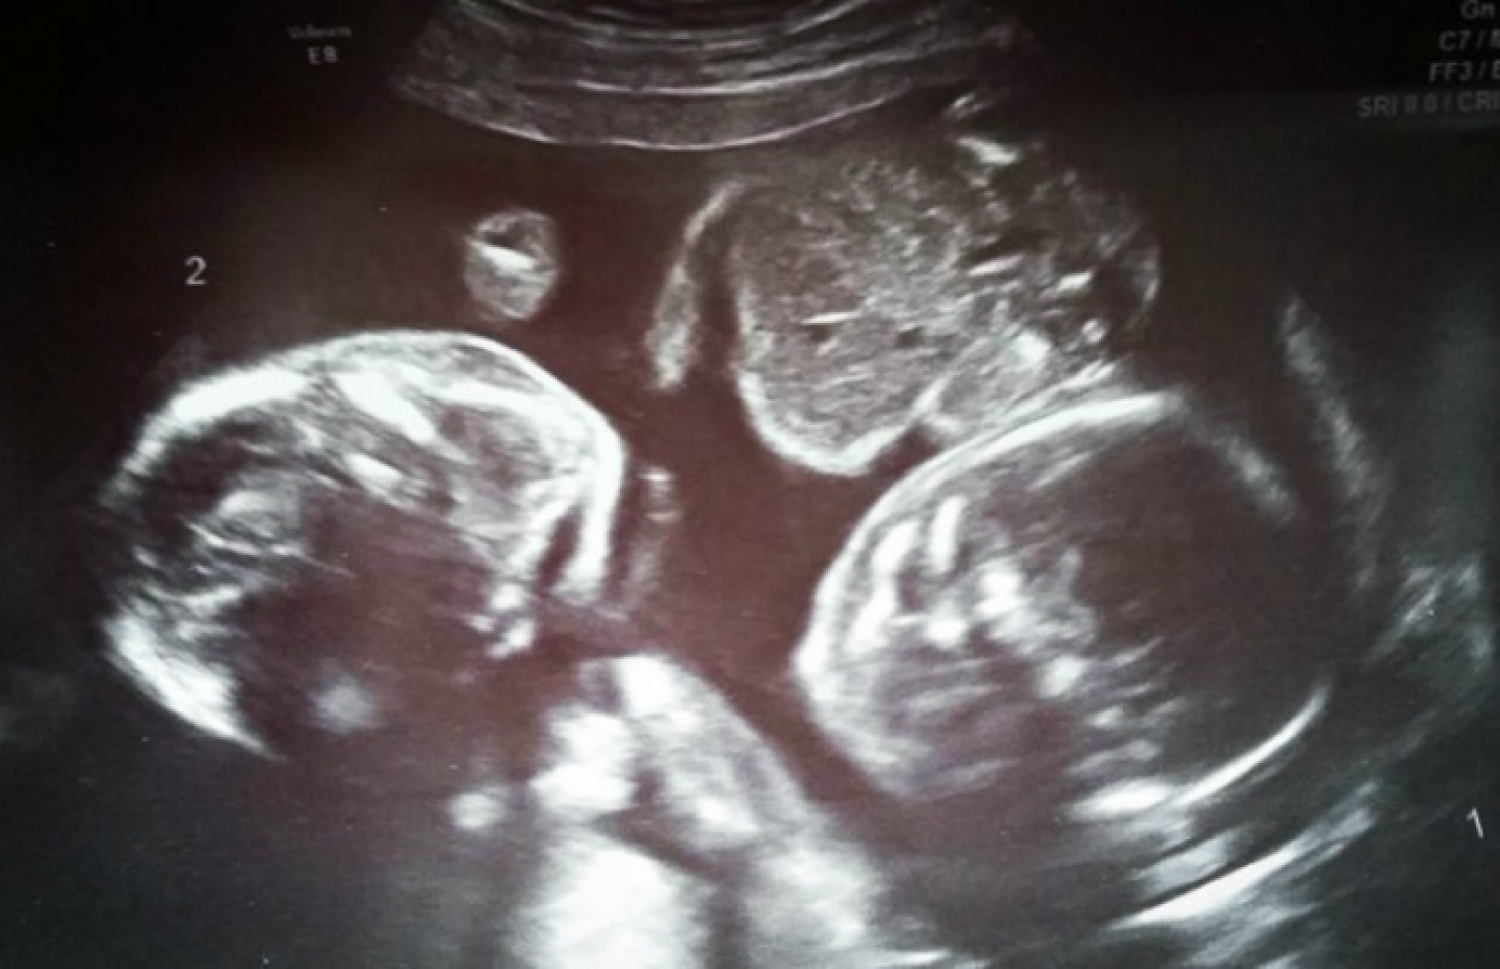

ބަނޑުގައި ތިބި ދެބެއިންނަށް ވެދާނެ ގޮތަކާ މެދު ފިކުރުބޮޑުވެފައި ހުރެފައި ބަނޑަށް 12 ހަފުތާގައި ހެދި ސްކޭނަށް ފަހު ހަމަޖެހުމެއް ލިބުނެވެ. ސޮނޮގްރާފަރު ބުނީ ކުދިން އެހެން ގޮތަކަށް އެނބުރިފައިވާ ކަމަށާއި މިހާރު ތިބީ ފުރާނަ ސަލާމަތްވާ ފަދަ ގޮތަކަށް ދެ ކުދިން އެއްކުއްޖަކު އަނެއް ކުއްޖެއްގެ ގައިގައި ބައްދާލައިގެން އަތާއިއަތް ގުޅާލައިގެން ކަމަށެވެ. އަދި ފޫޅުދަނޑި އޮޅިދާނެތީ އެކުދިން ތިބެނީ ހަރަކާތެއް ނުކޮށް ނުކޮށް ވަރަށް މަޑުމަޑުން ކަމަށް ވެސް ބުންޏެވެ.

ދެބެއިންގެ ފުރާނަ ސަލާމަތްވީ ބަނޑުތެރޭގައި ހަރަކާތެއް ނެތި އެއް ކުއްޖަކު އަނެއް ކުއްޖެއްގެ ގައިގައި ބައްދާލައިގެން ތިބުމުން.